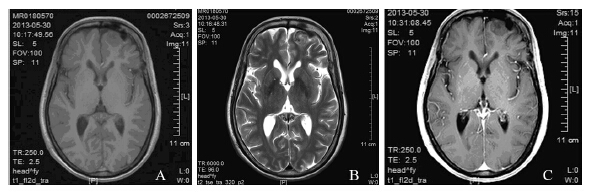

回顾性分析福建医科大学附属第一医院2012年6月—2014年11月手术治疗的7例MA。7例MA均为散发型,其中5例发生于右侧大脑半球,2例发生于左侧大脑半球。男性2例,女性5例,男女之比2:5。年龄4~56岁,平均17.86岁。首发症状为癫痫发作者5例,视物模糊者1例,发现肿块但无症状者1例,病程从1小时~10年。7例病例中收集到4例CT和4例MRI检查资料,其中6例表现为占位性病变。CT检查2例显示高密度钙化影,1例显示稍低密度影,1例显示低密度影;MRI检查结果分别为等T1短T2、长T1短T2、长T1等T2、等T1等T2各1例;对比增强扫描3例未见明显强化,1例明显均匀强化。典型病例例3见图 1。术前临床诊断困难,无一例诊断明确。7例均行肿瘤全切术,术后均未行放化疗。随访时间1~29月,均无复发,截止本次随访,所有病例无瘤生存,见表 1。

| MRI showed a lesion in the left frontal lobe (case 3), which was hypointensity on both T1(A)- and T2-(B) weighted imaging without enhancement(C) 图 1 散发型脑膜血管瘤病患者的MRI Figure 1 MRI f inding s o f spo r adi c meningioangiomatosis patients |

影像学特征对MA的诊断和鉴别诊断无明显特异性。本组病例中,CT和MRI错误提示为血管畸形、胶质瘤、钙化结节等。CT扫描显示病变通常为高或者稍高信号,伴钙化,但低或正常信号亦有报道。MRI表现各异,较常表现为T1低或等信号,T2显示信号不均匀,常为低信号。病变中钙化的高密度区显示T1和T2低信号。可表现为不均匀对比增强。MA在MRI上表现脑回状高信号是重要的影像学特征[7]。